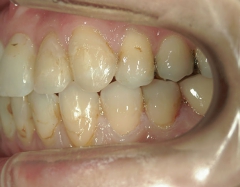

矯正歯科 治療後矯正歯科 全顎ワイヤー矯正 治療後矯正歯科(全顎ワイヤー矯正)治療後

治療期間2年6ヶ月

no.7_6967_治療後_右_01_640_480_やや高画質.jpgno.7_6967_治療後_正面_01.jpgno.7_6967_治療後_左_01.jpg